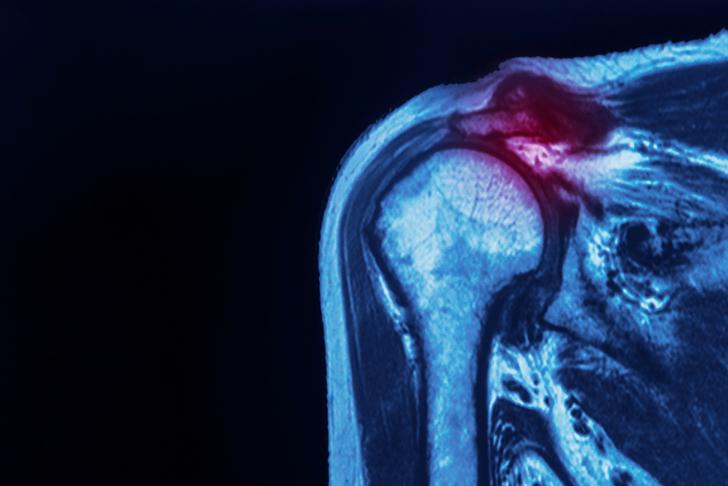

Rotator Cuff Injuries

Rotator cuff injuries are a common cause of shoulder pain and can result from tears, strains, or inflammation of the tendons and muscles that make up the rotator cuff [[2]]. These injuries often occur due to repetitive overhead movements or trauma and can cause pain, weakness, and limited range of motion in the shoulder.

Shoulder Impingement

Shoulder impingement occurs when the rotator cuff tendons become compressed and irritated as they pass through the narrow space beneath the acromion, a bony projection on the shoulder blade [[4]]. This can lead to inflammation, pain, and limited range of motion in the shoulder.